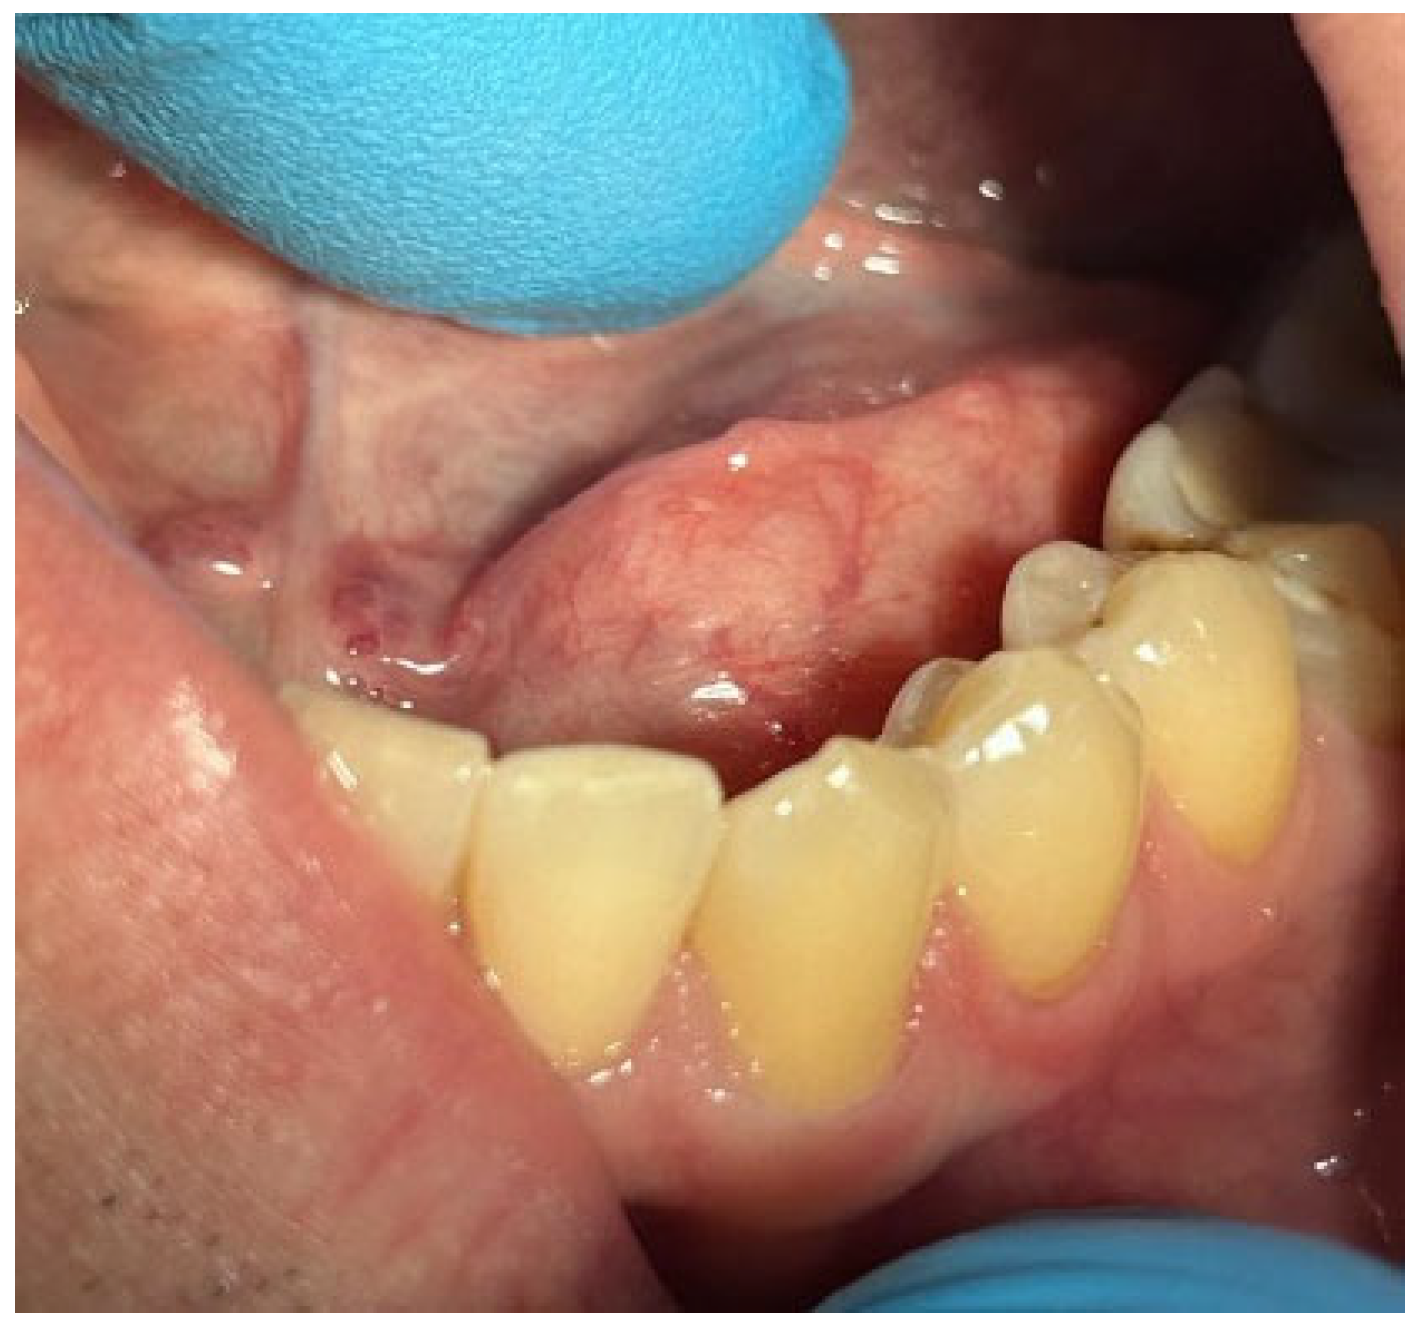

4.1. Clinical Case